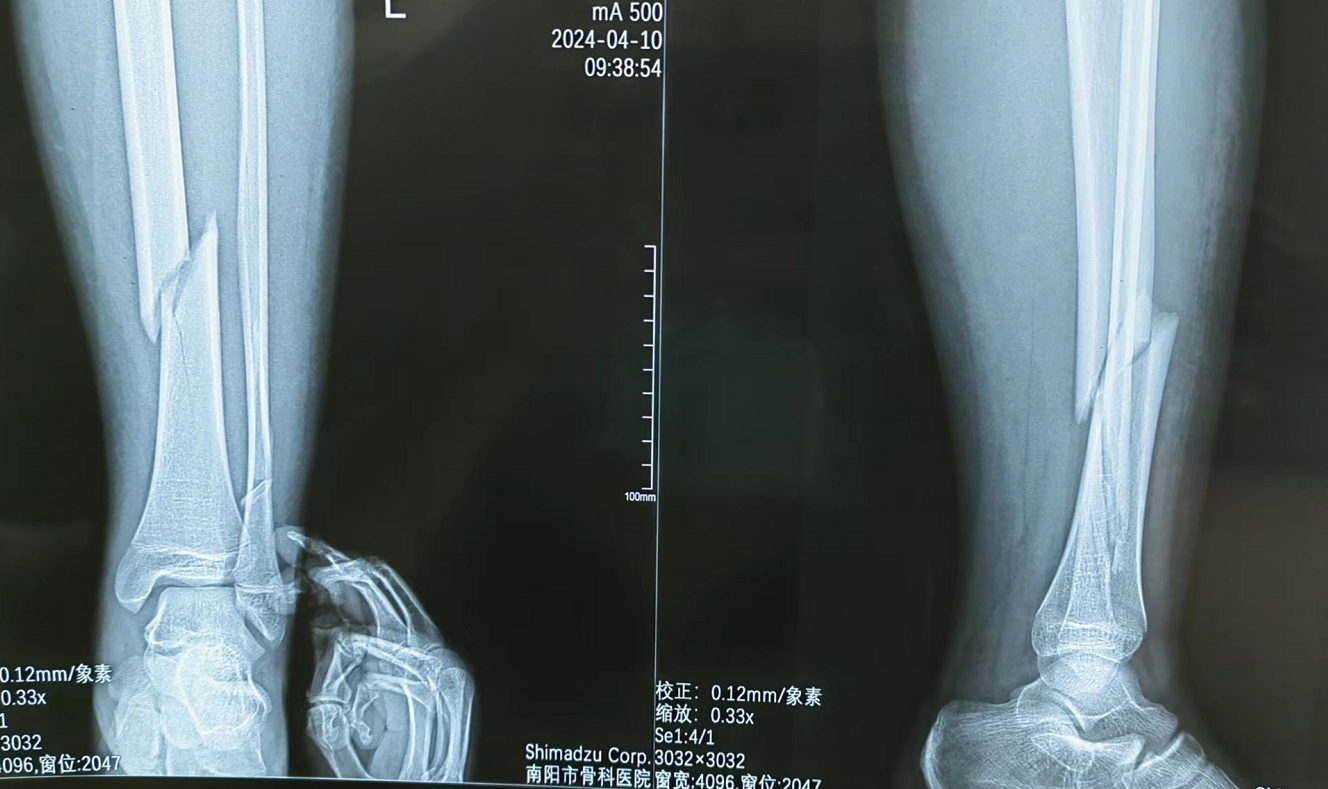

术前X片

本病例由中国中医科学院望京医院骨创伤一科提供【基本资料】患者,男,64岁术前X片···